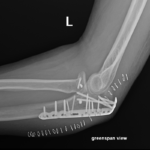

if the fracture is displaced, surgery may be needed to put the bone back into the correct position and fix the bone with Plates & screws or nails for adequate healing to occur.

- Elbow Fractures.